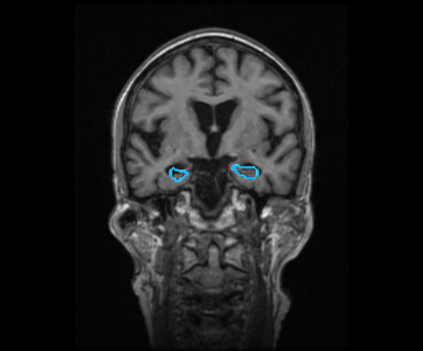

Radiomics uses quantitative medical imaging features to predict clinical outcomes. Currently, in a new clinical application, finding the optimal radiomics method out of the wide range of available options has to be done manually through a heuristic trial-and-error process. In this study we propose a framework for automatically optimizing the construction of radiomics workflows per application. To this end, we formulate radiomics as a modular workflow and include a large collection of common algorithms for each component. To optimize the workflow per application, we employ automated machine learning using a random search and ensembling. We evaluate our method in twelve different clinical applications, resulting in the following area under the curves: 1) liposarcoma (0.83); 2) desmoid-type fibromatosis (0.82); 3) primary liver tumors (0.80); 4) gastrointestinal stromal tumors (0.77); 5) colorectal liver metastases (0.61); 6) melanoma metastases (0.45); 7) hepatocellular carcinoma (0.75); 8) mesenteric fibrosis (0.80); 9) prostate cancer (0.72); 10) glioma (0.71); 11) Alzheimer's disease (0.87); and 12) head and neck cancer (0.84). We show that our framework has a competitive performance compared human experts, outperforms a radiomics baseline, and performs similar or superior to Bayesian optimization and more advanced ensemble approaches. Concluding, our method fully automatically optimizes the construction of radiomics workflows, thereby streamlining the search for radiomics biomarkers in new applications. To facilitate reproducibility and future research, we publicly release six datasets, the software implementation of our framework, and the code to reproduce this study.